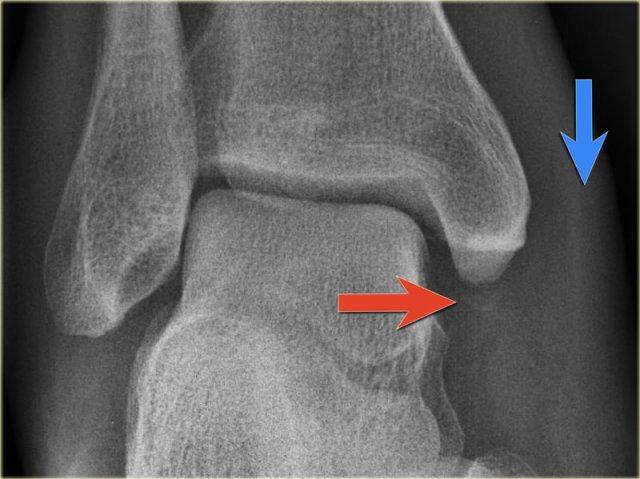

- Tái khám

Trên phim chụp cổ chân không có dấu hiệu gãy xương chéo của mắt cá ngoài, do đó chúng ta có thể loại trừ gãy xương Weber B.

Vẫn còn khả năng gãy xương Weber C giai đoạn 4, tức là đứt hoặc bong gân phía trong, gãy xương mác cao và cuối cùng là gãy mắt cá sau.

Khi tái khám, bạn nhận thấy hình ảnh bong điểm bám tinh tế của mắt cá trong (mũi tên đỏ), đây là giai đoạn 1.

Cũng lưu ý tình trạng sưng nề phần mềm ở phía trong (mũi tên xanh)

Các phim X-quang bổ sung của chi dưới được chỉ định và cho thấy gãy xương mác cao, tức là Weber C giai đoạn 3, còn được gọi là gãy xương Maisonneuve.

Final report

Weber C fracture stage 4.

This is un unstable ankle injury that needs surgical repair.